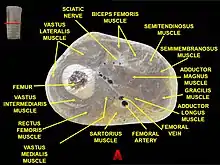

Muscles of thigh. Lateral view. Muscles of thigh. Cross section.

Muscles of thigh. Cross section. Distribution forces of the femur